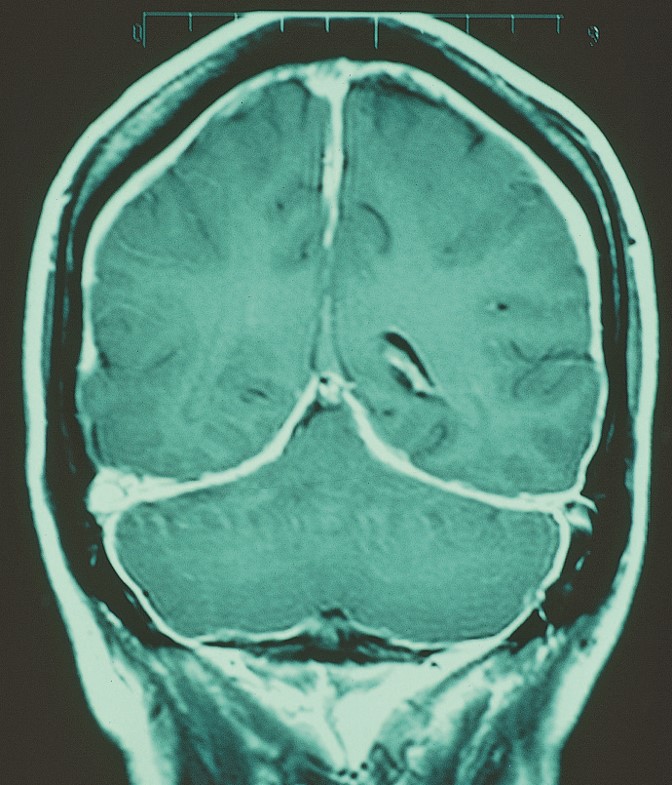

Dural enhancement from intracranial hypotension. A patient with a spontaneous cerebrospinal fluid leak presented with headache when sitting up or standing, relieved by lying down. Diffuse meningeal enhancement is seen in this magnetic resonance imaging scan of the brain (T1 sequence with contrast).

Source: Martin TJ, Corbett JJ. Practical Neuroophthalmology; 2013.